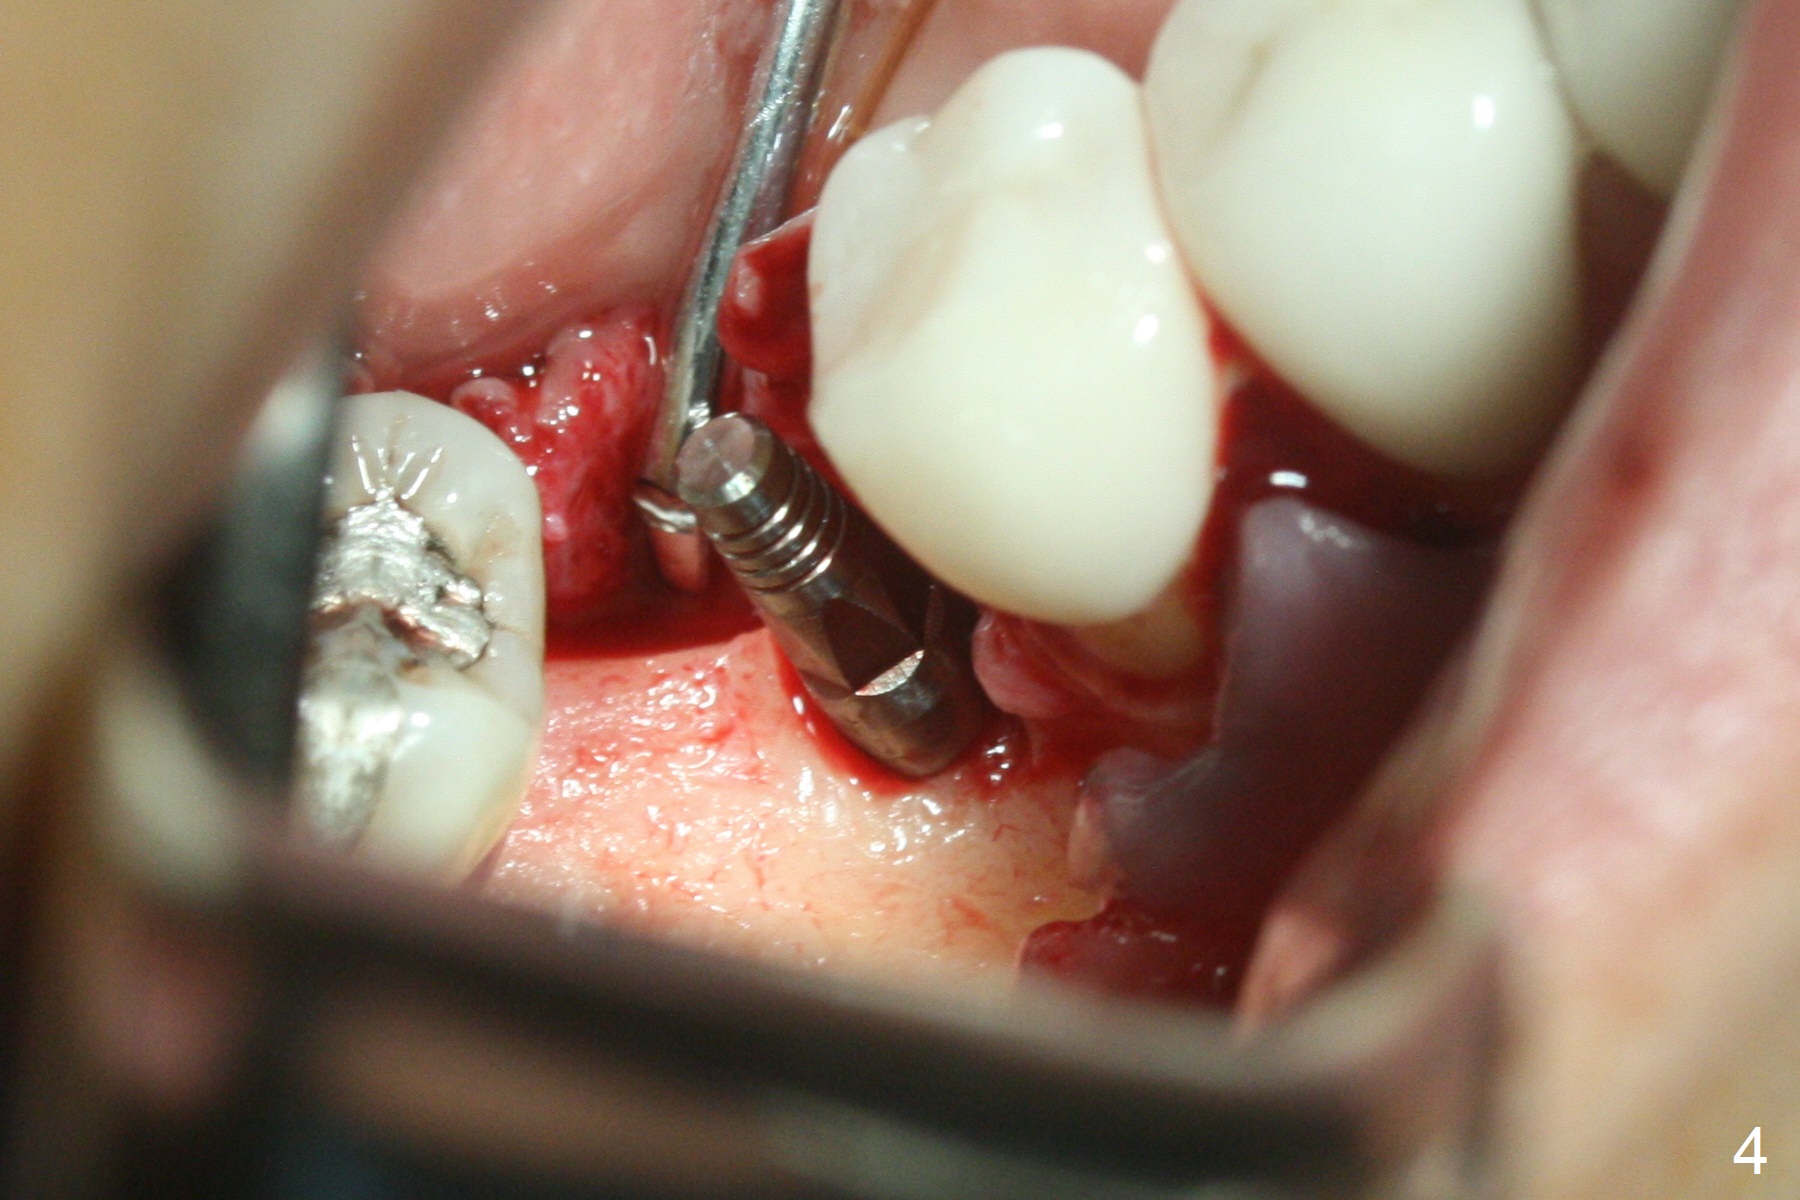

Incision reveals a narrow ridge and a narrow mesiodistal space at #30 (Fig.1). It seems that a 1-piece implant is indicated. Due to limited mouth opening, a 1.2 mm drill is unstable in place after use for 10 mm; instead a 1.5 mm drill is able to be inserted for 8 mm (Fig.2). A 3x10(2) mm 1-piece dummy implant is placed with 40 Ncm at an apparently acceptable level (Fig.3 >). Clinically a few threads are exposed buccally. When a definitive implant with the same dimension is inserted with 45 Ncm, it looks seated too deep (Fig.4,5). The latter is noted after suturing. The implant is backed up for a few turns so that the length of the abutment appears a little more reasonable. Introspectively, a 4 mm cuff should have been used after ridge reduction. Although there is no bone loss 4 months postop (Fig.6), the abutment margin (Fig.7 arrow) is subgingival (red dashed line: gingival margin). Diode laser is used for gingivectomy prior to impression. The bone density around the implant increases 11 months post cementation (Fig.8 *), probably related to recurrent #18 infection. The patient uses floss after meal.